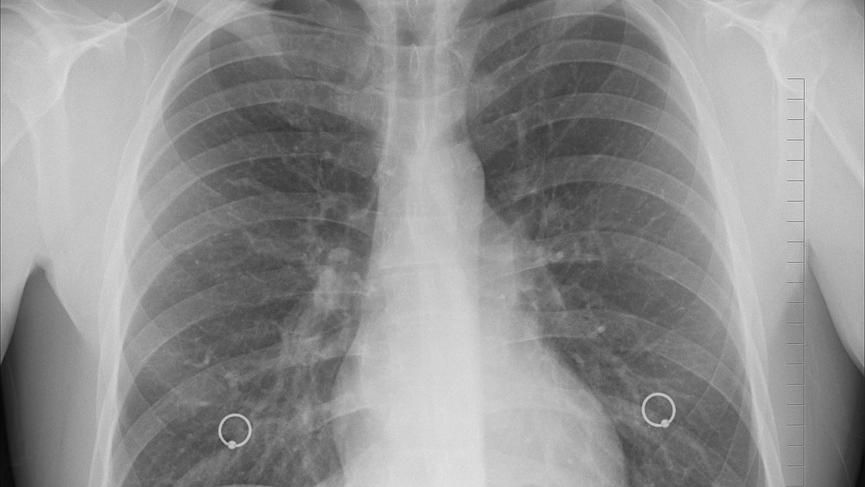

台南一名67歲退休焊接工陳姓男子,菸齡長達40年,受慢性阻塞性肺病困擾超過15年,即便已戒菸5年,肺功能仍重度受損肺活量僅餘29%,夜間需依賴氧氣設備。奇美醫院中醫部主治醫師梁祐爾診斷,發現病患「痰瘀互結、營衛不調、腎氣虛」,經中藥調理兩週後,終於大幅改善。

奇美醫院中醫部主治醫師梁祐爾診斷後,發現陳男有慢性阻塞性肺(OPD),通常這類型病患不只是肺部問題,常合併心血管疾病、睡眠障礙、營養不良及肌少症,形成惡性循環。梁祐爾說,長期抽菸會破壞肺部結構,使呼吸道長期發炎且難以完全恢復。